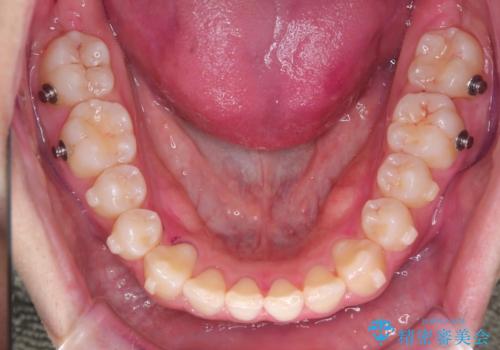

- 八重歯が気になるとのことでご来院されました。お口の中を確認すると、上の前歯がスペース不足で押し出され、少し前に出ている状態でした。抜歯せずに整えるため、奥歯を少しずつ後ろに動かしながら(遠心移動)、歯と歯の間をわずかに削るIPRを行ってスペースを作ることにしました。また、上下の噛み合わせを整えるために2級ゴム(エラスティック)を使用する方針を立てました。

マウスピースを段階的に交換しながら、奥歯を少しずつ後ろへ動かし、八重歯がきれいに並ぶよう調整しました。前歯の突出感を抑えるためにIPRを行い、スムーズに配列。さらに、2級ゴムを活用して噛み合わせも改善しました。治療後は、自然な歯並びになり、笑顔に自信が持てるようになったと喜んでいただきました。